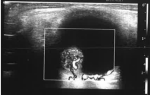

Démarche diagnostique: l'angiographie à la fluorescéine a montré une lésion hypo-fluorescente au temps précoce, devenant hyper-fluorescente au temps tardif, avec persistance d'un centre hypo-fluorescent (Figure 1 B). L'échographie oculaire (Figure 2) ainsi que l'imagerie par résonance magnétique (Figure 3) ont révélé une masse choroïdienne, saillante, en dôme ou en champignon, bien limitée para-maculaire supérieure, compatible avec une tumeur intraoculaire. Les caractéristiques qui ont été rapportés sont: masse tissulaire hyperéchogènes, hétérogène, de contours nets, hypervascularisée, siégeant à droite du nerf optique, mesurant 7x7 mm.

Figure 2: échographie oculaire montrant une lésion en relief, d'aspect classique en dôme ou en champignon, vascularisée au doppler